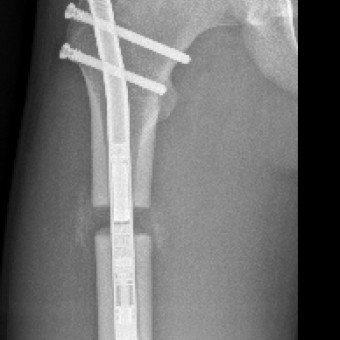

Die Knochenverlängerung mit dem magnetgetriebenen Marknagel Precice® hat sich als bedeutendste technologische Innovation in der Extremitätenrekonstruktion etabliert. Bei dieser Methode wird der getrennte Knochen durch Callusdistraktion täglich um etwa 1 mm verlängert. Im Vergleich zu externen Fixateuren ist diese vollimplantierte Lösung für Patientinnen und Patienten deutlich angenehmer und weniger schmerzhaft.

Die Ergebnisse sind ausgezeichnet und Komplikationen selten. Im schweizerischen Vergleich gehören wir auf diesem Gebiet zu den führenden Kliniken.